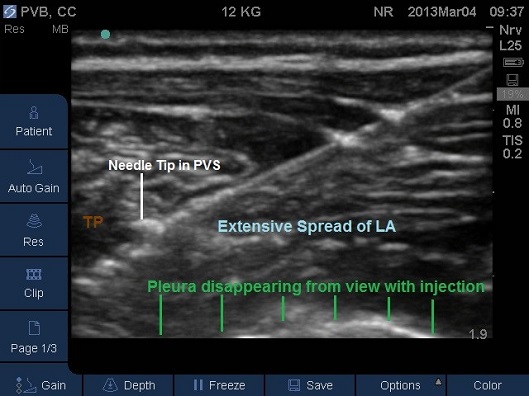

- Correct placement of the needle in the thoracic Paravertebral space should be confirmed by the anterior displacement of pleural upon injection of a small bolus of saline or local anaesthetic (Fig 13-16).

- Once confirmed the required volume of local anaesthetic should be injected.

Fig 15. Paravertebral space entered by needle, pleura displaced anteriorly by local anaesthetic. TP –transverse process. Local anaesthetic spread marked in light blue

Fig 16. Paravertebral space filled by local anaesthetic. TP –transverse process.